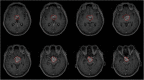

Methods: Forty-four patients pathologically diagnosed as adamantinomatous craniopharyngioma (ACP) or papillary craniopharyngioma (PCP) were retrospectively studied. High-throughput features were extracted from manually segmented tumors in MR images of each case. The modifications-robustness in region of interests and Random Forest-based feature selection methods were adopted to select the most significant features. Random forest classifier with 10-fold cross-validation was applied to build our radiomics model.

Results: Four features were selected to make pathological diagnosis between ACP and PCP with area under the receiver operating characteristic curve (AUC) of 0.89, accurancy (ACC) of 0.86, sensitivity (SENS) of 0.89 and specificity (SPEC) of 0.85. The other two features were applied to estimate BRAF V600E mutation with AUC of 0.91, ACC of 0.93, SENS of 0.83 and SPEC of 0.97. Accurate predication of CTNNB1 mutation by three selected features was realized with AUC of 0.93, ACC of 0.86, SENS of 0.86 and SPEC of 0.86.